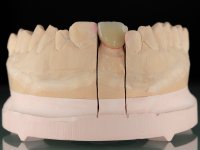

The endocrown should be constructed with a zirconia framework with an ‘intra-root’ and crown components, being this last one veneered with ceramics.

CAD-CAM technology was used to design and construct an endocrown with a zirconia framework veneered with ceramics. The crown was then bonded to the tooth, by using an MDP based adhesive and a dual polymerization composite resin.